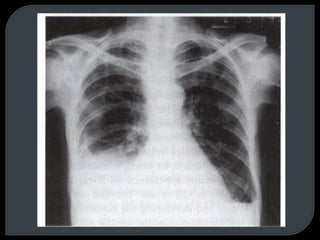

This document discusses x-rays and radiographic views. It begins with the discovery of x-rays by Wilhelm Conrad Roentgen. It then covers basic concepts like radiopacity and radiolucency. Several standard radiographic views are described like AP, PA, lateral, and decubitus. The document outlines how to analyze a chest x-ray using the ABCD method and lists common abnormal radiological signs. Radiographic technique factors like centering and inspiration level are also addressed.